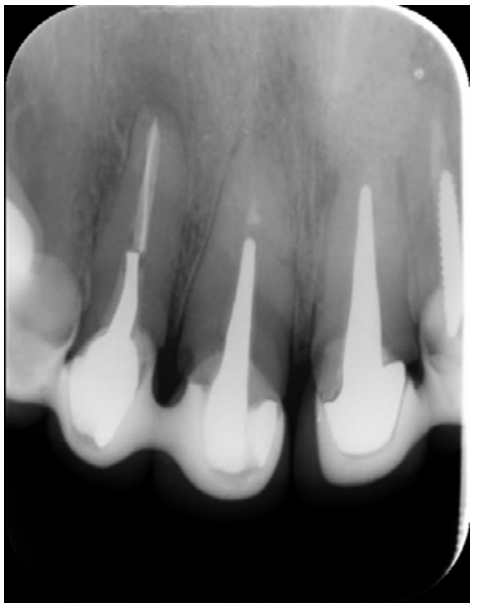

The patient provided an orthopantomography (OPG) as a radiological study (Figure 1). Periapical radiographs (Figures 2 and 3) were performed and a clinical examination including periodontal assessment of the affected teeth, without observing increased probing depths that could indicate the existence of endoperiodontal lesions.

To confirm the endodontic origin and the size of the lesions, tomographic examinations were performed with a slice thickness of 75 microns using CBCT CS8100 (Carestream Dental™), in which radiolucent periapical lesions were observed at the level of 12, 11, 21 (with bicortical involvement), 25 and vestibular roots at 26 (Figures 4 to 8).